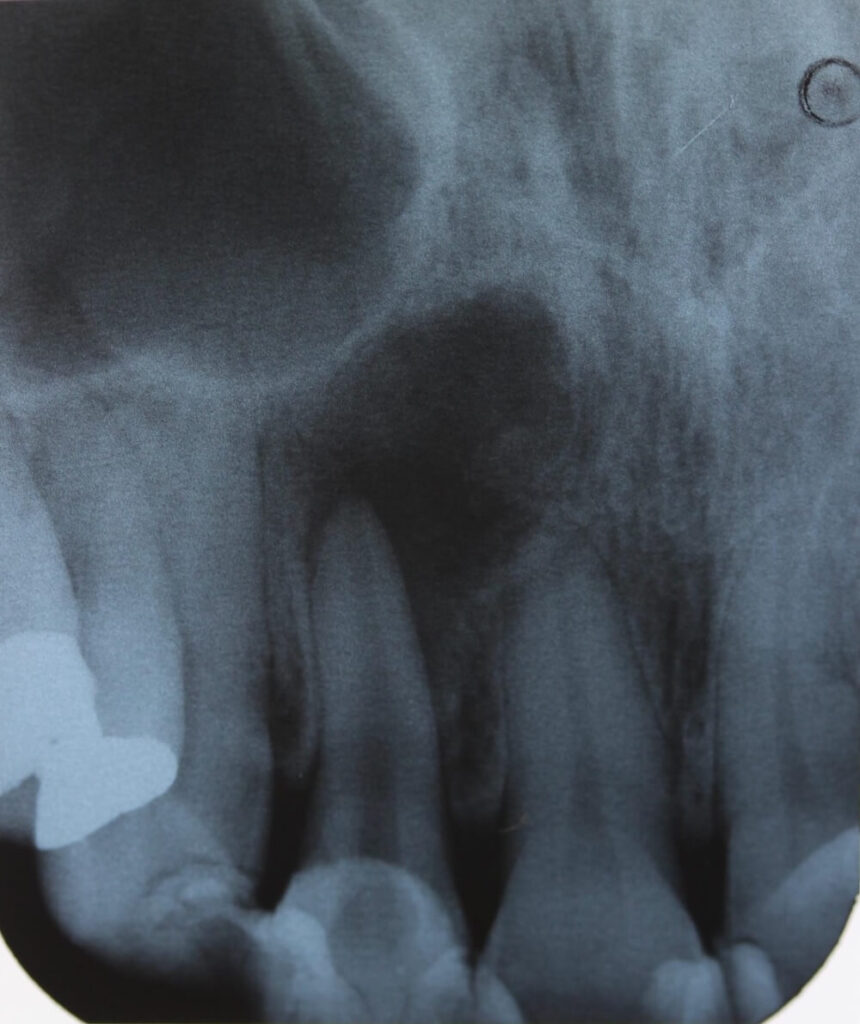

レントゲン(デンタルX線)では 根の先に2cm以上の大きな骨吸収 が確認されました。

初診時、上あごの裏側(口蓋)が大きく腫れあがり、膿がたまっている状態でした。

腫れと痛みを緩和するため切開排膿を行うと、内部から大量の膿が排出されました。

根の先の形態は、これまでに何度も治療が繰り返されていた影響で 大きく開いている状態(拡大・変形) でした。